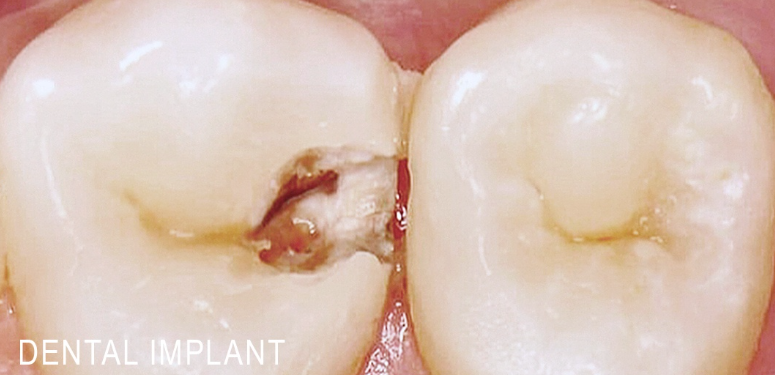

3 работы в портфолио